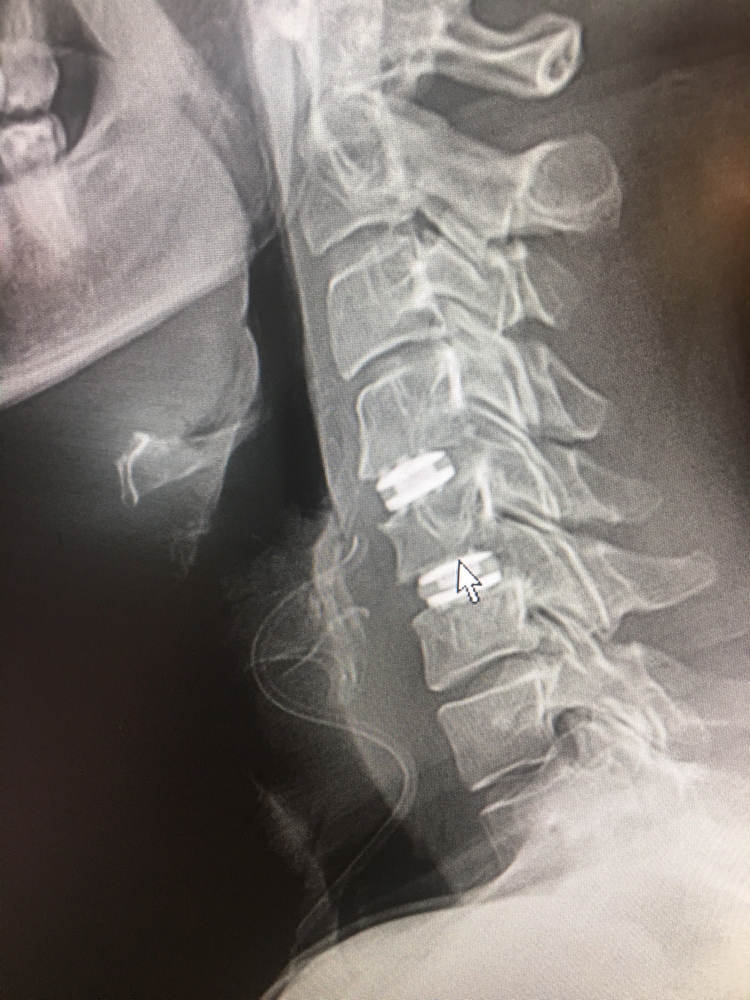

Phẫu thuật cắt đĩa đệm cổ lối trước và cố định đốt sống (Anterior Cervical Discectomy and Fusion – ACDF) từ lâu đã được xem là tiêu chuẩn vàng trong điều trị đau và/hoặc thiếu hụt dẫn truyền thần kinh do viêm rễ thần kinh và/hoặc chèn ép tủy sống ở cột sống cổ.

Điểm giống nhau của 2 phương pháp ACDF và thay đĩa đệm cổ nhân tạo (C-ADR) là loại bỏ chèn ép và phục hồi chiều cao bình thường, và tuy nhiên chúng khác biệt ở chỗ ACDF làm cứng các đốt sống liền kề, do đó mất đi vận động tại đoạn cột sống đó. Trong những trường hợp ACDF và C-ADR đều là các lựa chọn khả thi, một số lợi ích tiềm năng khi chọn C-ADR có thể bao gồm: